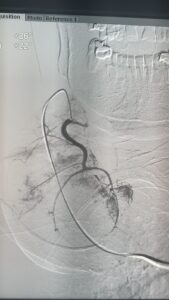

فى إنجاز طبى غير مسبوق داخل مصر، بل و على مستوى الشرق الأوسط، أعلن الدكتور محمود عبد العزيز غلاب – استشارى الأشعة التداخلية – عن نجاحه فى إجراء أول حالة من نوعها فى الأسكندرية لعلاج تضخم الغدة الدرقية عن طريق القسطرة الشريانية، و هو أسلوب حديث تم نقله من اليابان بعد تدريبه فى واحدة من أرقى الجامعات اليابانية المتخصصة في مجال الأشعة التداخلية.

تعد هذه الحالة الأولى من نوعها التى يتم فيها الدخول عبر القسطرة الشريانية إلى الشرايين المغذية للغدة الدرقية في الإسكندرية.

المريضة، وهى سيدة تبلغ من العمر 81 عامًا، كانت تعانى من تضخم شديد بالغدة الدرقية تسبب فى ضغط على القصبة الهوائية، مع تعدد النتوءات داخل الغدة، إلى جانب معاناتها من أمراض بالقلب حالت دون إمكانية خضوعها لأى جراحة. و بعد رفض حالتها من قِبل أكثر من استشارى جراحة نظراً لخطورة التدخل الجراحى، كان الحل الوحيد هو اللجوء إلى الأشعة التداخلية.

و بسبب كبر حجم الغدة و تعدد النتوءات فيها، لم يكن التردد الحرارى هو الخيار الأمثل، وعليه و بالتنسيق مع الدكتور محمد جلال الغاوي استشاري الغدد الصماء فقد قام الدكتور محمود غلاب أسلوبًا بالتدخل عبر الحقن بالقسطرة الشريانية، وهو ما مكّن من غلق الشرايين المغذية للنتوءات وبالتالى تقليص حجمهم و تحسين الأعراض بشكل ملحوظ.